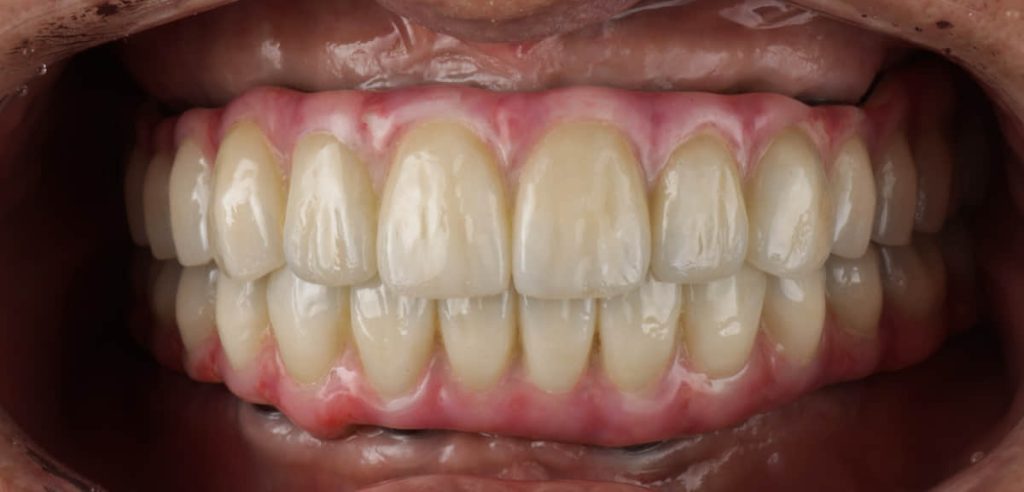

術後正式假牙

術後配戴正式假牙